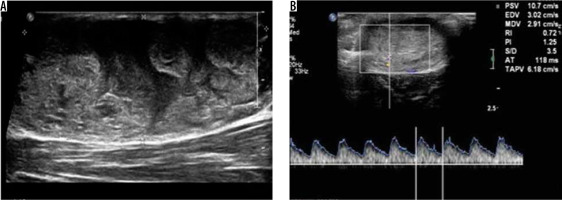

Figure 7

Schwannoma with cavernous malformation – greyscale ultrasound image (A) shows a well-defined heterogeneously hyperechoic lesion. Spectral Doppler image (B) of the same lesion shows internal vascularity with arterial waveform